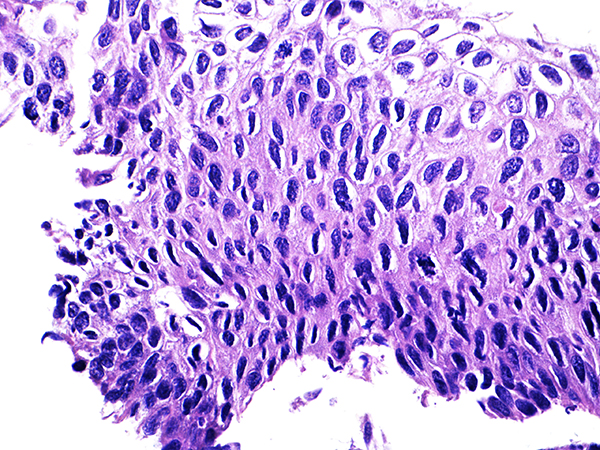

![]() Case 1

Area 2 - Soft Bx CIN 2 40x - High Power |